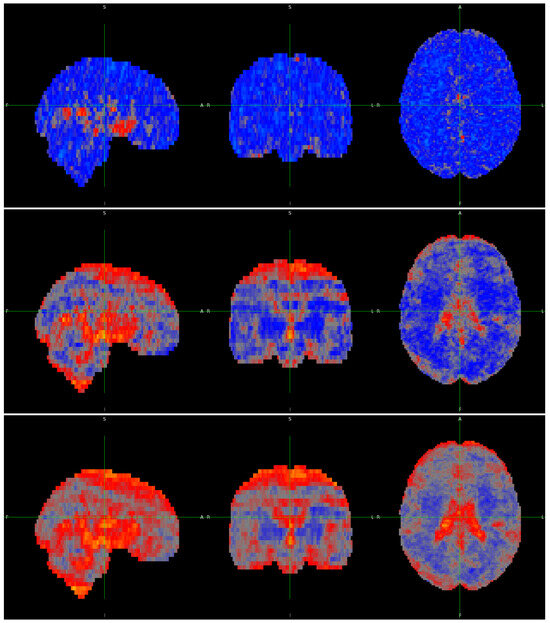

3. Results